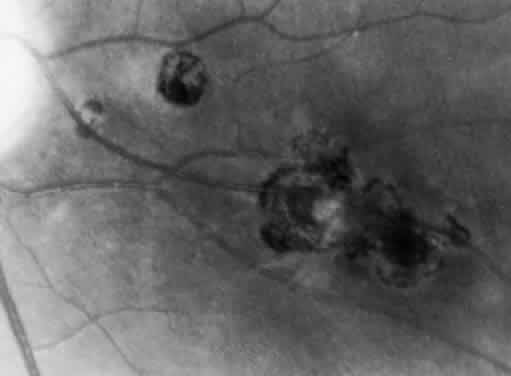

Bradyzoites are slowly metabolizing organisms found in cysts formed within the tissue of the infected host. The size of the Toxoplasma cyst varies, depending on the number of organisms that have multiplied within it. The cyst may reach more than 100 μm in diameter and may contain from 50 to 3000 organisms. The cyst wall is strongly argyrophilic and periodic acid-Schiff positive. It contains constituents that are derived from both the parasite and the host tissue. Constituent from the host tissue compose the outer part of the cyst, whereas those derived from the parasite are in the inner part of the cyst wall. Toxoplasmosis may be found in the inner layers of the retina after episodes of acute retinochoroiditis. The cyst may stay in the retinal tissue for years without showing any signs of invasiveness. Considering that the tissue cyst incorporates elements derived from the host into its outer wall, it is easily tolerated by the host, and no inflammatory reaction is seen around it (Fig. 2). It may remain for years in certain tissues, such as the eye or muscles, without provoking any inflammatory reactions. The bradyzoite inside the cyst derives its nutrition from the slow diffusion of substances through the cyst wall. The number of organisms increases within the cyst in the retina, and once the cyst wall breaks down by mechanical stretching, the bradyzoites escape, convert into tachyzoites, and invade contiguous cells. This process may lead to recurrence of retinitis. Certain immunologic mechanisms of the host may influence the organisms significantly. Immunosuppression coinciding with the rupture of the cyst and release of bradyzoites allows the organisms to become tachyzoites and proliferate in host tissue without restriction. The cyst of the Toxoplasma organism appears to be a defensive stage in its life cycle. The resistance of toxoplasmosis within chronically infected tissues of animals may lead to transmission of the disease by the ingestion of undercooked meat, including mutton, beef, pork, and chicken. Tissue cysts can develop within any organ and are commonly found in infected tissues of brain, eye, heart, skeletal muscles, and lymph nodes. Rupture of tissue cysts causes reactivation of the systemic toxoplasmosis in immune deficiency states, leading to dissemination of Toxoplasma organisms to other organs.